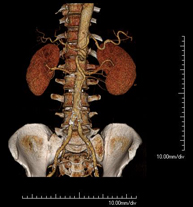

- Abdominal aorta CT angiography

A non-invasive diagnostic test that involves studying the abdominal aorta by obtaining high-definition anatomical images using CT (computed tomography) equipment and iodinated contrast. With the aid of workstations specialised for arterial studies, the image quality supports 2D and 3D reconstructions. It is indicated in patients with vascular disease (atherosclerosis), aortic aneurysms, abdominal pain of possible vascular origin, pre-surgical studies of lesions adjacent to the abdominal aorta as a vascular ‘map’, etc. Information obtained non-invasively is indispensable for patients requiring percutaneous or surgical processing. In patients who only require tracking of vascular lesions, this technique is the non-invasive technique of choice, together with MRI angiography.

- Renal artery CT angiography

A non-invasive diagnostic test that involves studying the renal arteries by obtaining high-definition anatomical images using CT (computed tomography) equipment and iodinated contrast. With the aid of workstations specialised for arterial studies, the image quality supports 2D and 3D reconstructions. This test is recommended, for example, in patients suffering from refractory hypertension that does not respond to processing, in patients with kidney damage in order to obtain a pre-surgical ‘vascular’ map, etc.

- Aortoiliac CT angiography

A non-invasive diagnostic test that involves examining the iliac arteries and abdominal aorta, obtaining high-definition anatomical images using CT (computed tomography) equipment and iodinated contrast dye. With the aid of workstations specialised for arterial studies, the image quality supports 2D and 3D reconstructions. This test is particularly recommended as a pre-surgical study (vascular map) prior to percutaneous or surgical interventions on the abdominal aorta, as a complementary study in patients with lower limb ischaemia, etc.